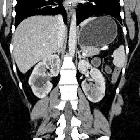

adult polycystic kidney disease (APCKD)

Autosomal dominant polycystic kidney disease (ADPKD), also sometimes more vaguely referred to as "adult polycystic kidney disease", is as the name would suggest, a hereditary form of adult cystic renal disease.

Radiographic features

Imaging of patients with autosomal dominant polycystic kidney disease can be challenging, simply due to the size and number of the cysts and associated mass effect on adjacent structures. It is potentially tedious, but necessary, to assess all cysts for atypical features, that may reflect complications (e.g. hemorrhage or infection) or malignancy (i.e. renal cell carcinoma) .

CT

CT is of course very sensitive to the diagnosis and excellent at characterizing renal cysts. Simple cysts appear as rounded structures with near water attenuation (~ 0 HU). The wall is very thin and regular, and are often imperceptible.

Cysts which have had internal complications may be hyperattenuating, with internal non-enhancing septations and/or calcifications.

A complex cystic mass with solid components or thick septa which enhance should be viewed with suspicion, and presence of a renal cell carcinoma (RCC) suspected (see Bosniak classification of renal cysts).